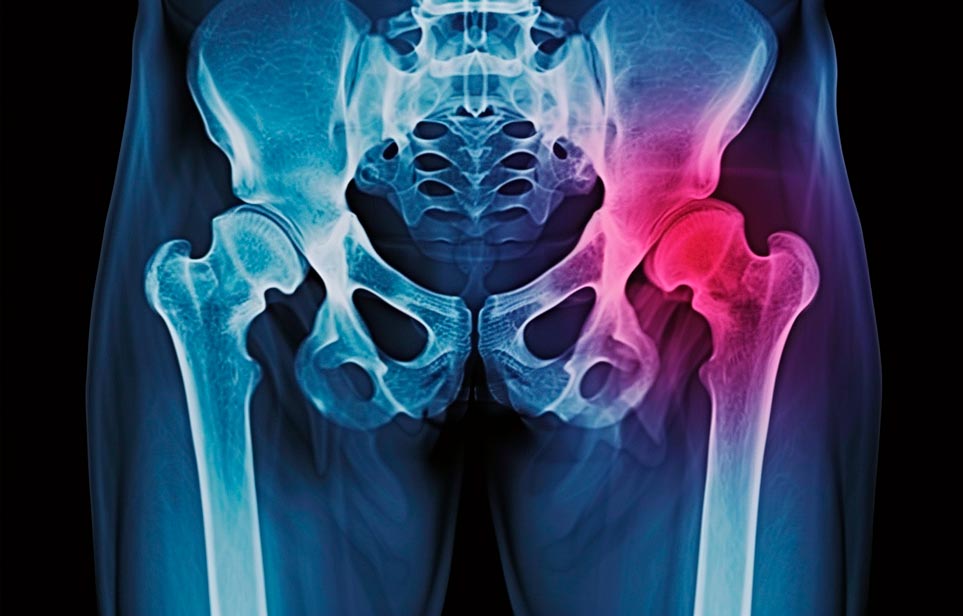

Реабилитация пожилых после перелома шейки бедра в Феодосии

Такая травма в большей части случаев возникает у граждан преклонного возраста. При её появлении на протяжении длительного времени сохраняются болевые и неприятные ощущения в области паха, при которых серьёзно ухудшается качество жизни, возникает множество последствий для его жизни и здоровья.

По какой симптоматике можно определить перелом шейки бедра?

Выявить его можно по возникновению следующей тревожной симптоматики:

- Визуально повреждённая нога сокращается на несколько сантиметром из-за сокращения мышц.

- Стопа выворачивается наружу.

- В лежачем положении человек не может поднять ногу.

При такой симптоматике важно незамедлительно обращаться к специалистам для получения всей необходимой помощи, терапии и восстановления после перелома шейки бедра. Если не оказать помощи старику, то это приведёт к гноению, инвалидности, иным видам осложнений.